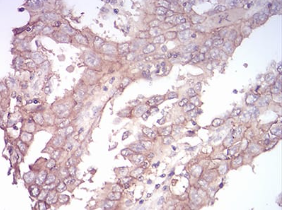

SK2 Mouse Monoclonal antibody[9C5E1]

This gene encodes one of two sphingosine kinase isozymes that catalyze the phosphorylation of sphingosine into sphingosine 1-phosphate. Sphingosine 1-phosphate mediates many cellular processes including migration, proliferation and apoptosis, and also plays a role in several types of cancer by promoting angiogenesis and tumorigenesis. The encoded protein may play a role in breast cancer proliferation and chemoresistance. Alternatively spliced transcript variants encoding multiple isoforms have been observed for this gene.

Species Reactivity:    Human

Immunogen:    Synthesized peptide of human SK2 (AA: 36-52).

IHC    1/200 - 1/1000